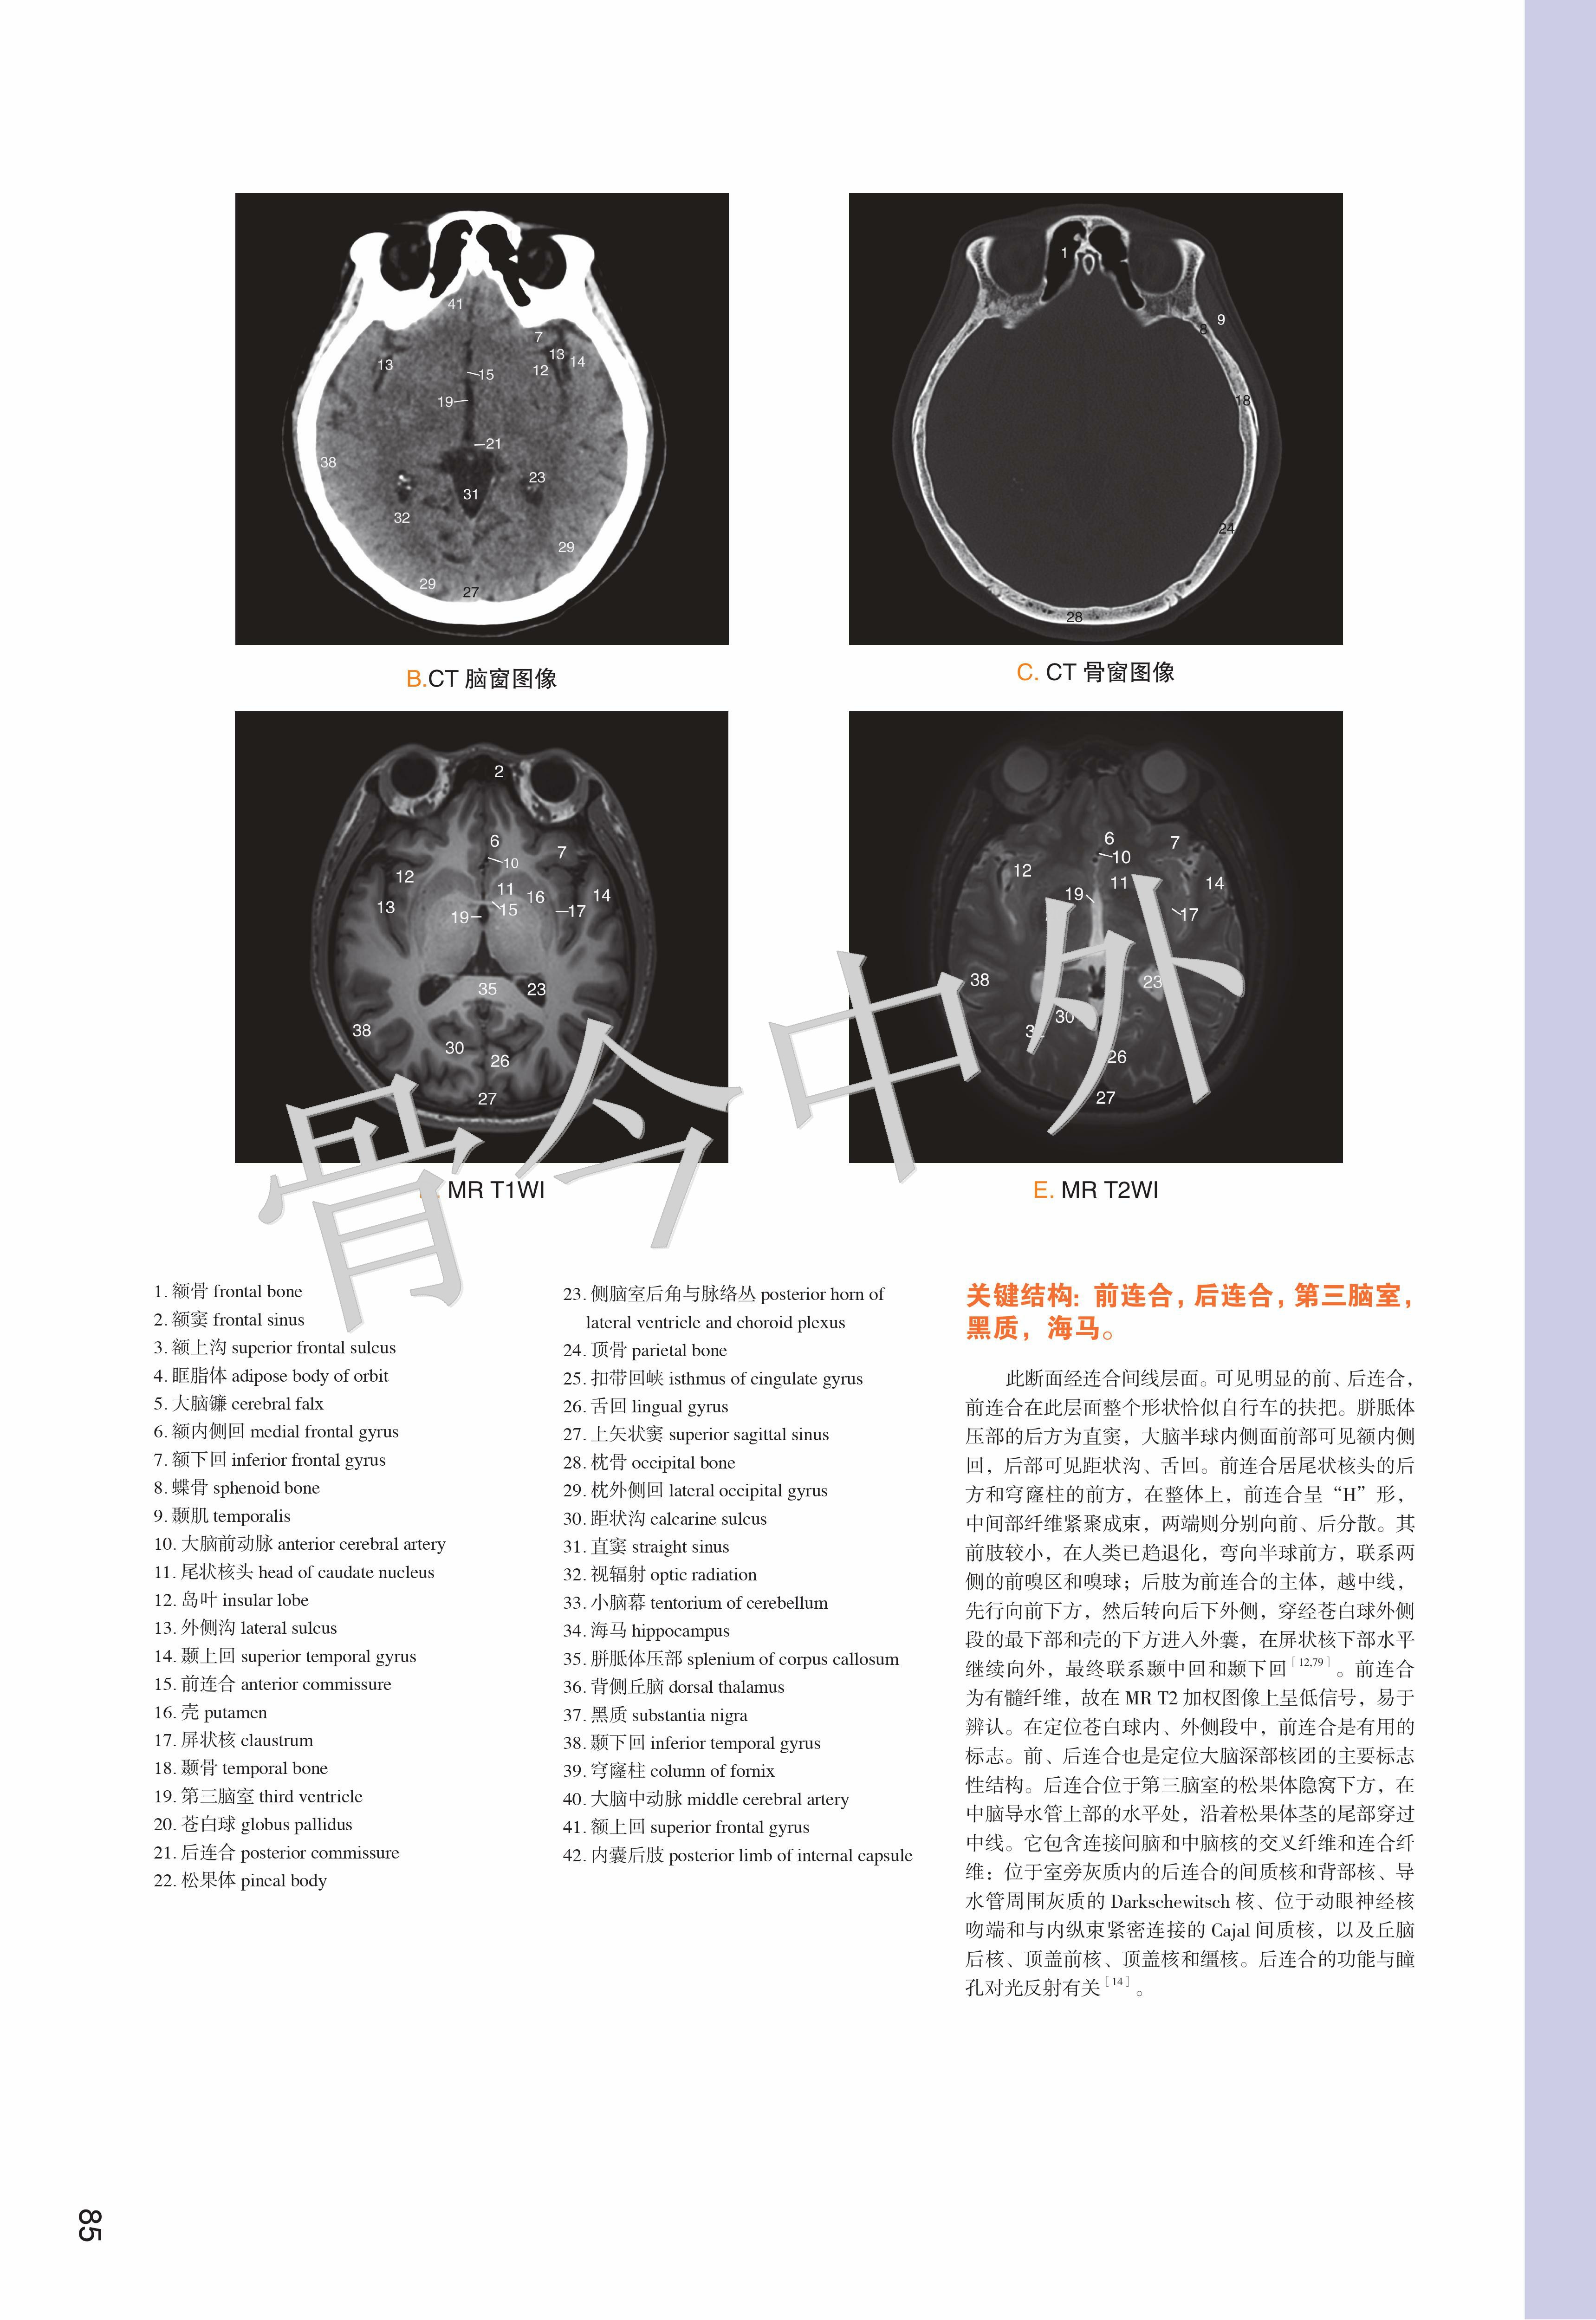

《数字人连续横断层彩色解剖学图谱·头颈部分册》包括三篇:第一篇简述了人体断层数据获取方法,第二、三篇分别介绍了头部和颈部的薄层连续横断层解剖及 CT、MR 图像。本例头部标本共有 101 层,由上而下可分为 6 段。 第1段,16050 ~ 15570 层面,共 25 层,胼胝体尚未出现,主要的解剖结构有头皮、颅顶骨、蛛网膜粒、上矢状窦与大脑上静脉、大脑镰、大脑额叶与顶叶;第 2 段,15550 ~ 15270 层面,共 15 层,以胼胝体出现为标志,主要表现为颞肌、脑颅骨、胼胝体、侧脑室、大脑主要沟回、基底核区与间脑、大脑前动脉、大脑中动脉和大脑外侧窝池;第 3 段,15250 ~ 15090 层面,共 9 层,从前后连合层面至垂体出现层面,主要出现枕额肌与颞肌、脑颅骨、大脑半球(颞叶、枕叶与边缘叶)、上丘脑与后丘脑、中脑、脑桥、第 1 4 脑神经、脑血管(大脑前、中、后动脉)、小脑幕、蝶鞍区和视器;第 4 段,15070 14730 层面,共 18 层,从垂体出现至寰枕关节层面,由前向后,主要出现眶下部、鼻腔与鼻旁窦、蝶鞍区与颅中窝(第 5 12 对脑神经、脑血管、海绵窦、垂体、大脑颞叶与枕叶)、颞骨岩部和颅后窝(脑桥、延髓、小脑),其间充填以颌面筋膜间隙;第 5 段,14710 ~ 14390 层面,共 17 层,从寰枕关节至下牙槽出现层面,主要出现口腔(重点为舌)、腮腺咬肌区和枕骨大孔区(重点为小脑扁桃体、颈静脉孔区和脑血管);第 6 段,14370 ~ 14050 层面,共 17 层,从下牙槽出现至下颌骨消失层面,主要出现下颌骨、口底结构(舌、三大唾液腺)、颈动脉鞘、颈外动脉及其分支和淋巴结。颈部上方从枕骨大孔平面开始,下方至胸骨颈静脉切迹平面结束,共有 82 层,由上而下,可分为 4 段。第1段,10500 ~ 10020 层面,共 25 层,从枕骨大孔平面至舌骨大角平面,断面前份为颌面部结构,后份为脊柱区颈段,两侧为颈动脉鞘;第2段,10000 ~ 9430层面,共 30 层,从舌骨大角平面至环状软骨下缘平面,颈部断面可明显地区分为四个格,即前份的内脏格(咽、喉、甲状腺侧叶和甲状旁腺)、两侧的血管神经格(颈动脉鞘)和后份的支持格(脊柱区颈段);第3段,9420 ~ 9330 层面,共 10 层,从环状软骨下缘平面至第 1 胸椎体上缘平面,内脏格表现为气管、食管、甲状腺和甲状旁腺,血管神经格和支持格同上;第4段,9320 ~ 9160 层面,共 17 层,从第 1 胸椎体上缘平面至胸骨颈静脉切迹平面,主要为颈根部,重点关注斜角肌间隙、星状神经节、胸膜顶和肺尖等。